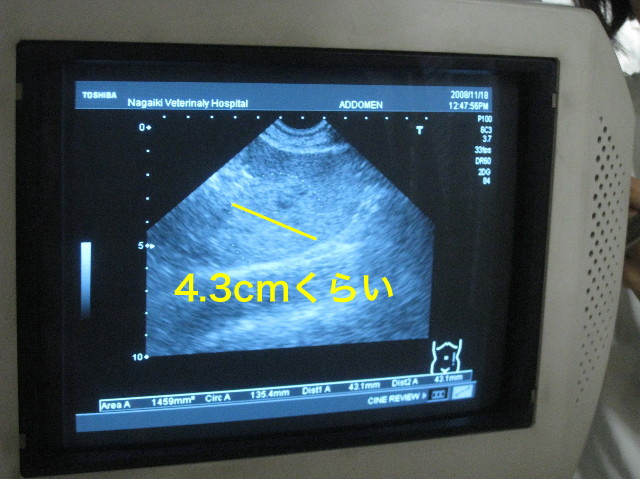

11月18日のエコーに写っていた病変部分。(1週間で約倍の大きさになっていた)